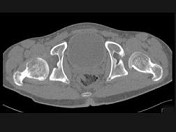

男,23岁,跛行,外展受限,两下肢不等长,结合图像,最可能的诊断是()

• A.髋关节中心脱位

• B.髋关节后脱位

• C.髋关节前脱位

• D.先天性髋内翻

• E.髋关节结核